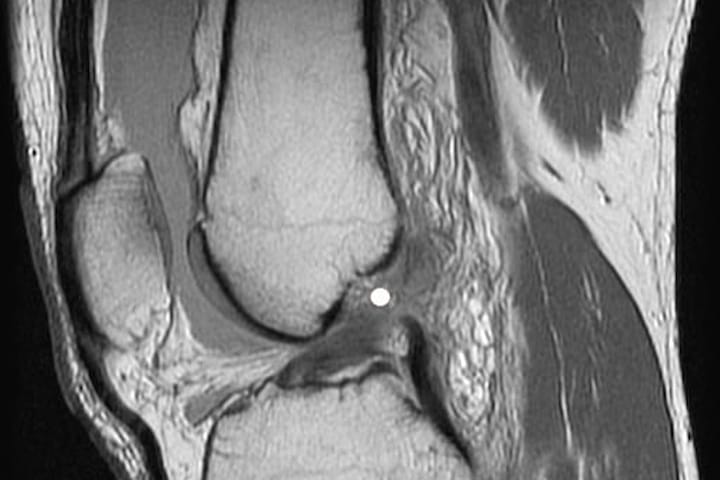

Диагностика и особенности гемартроза плечевого сустава на МРТ